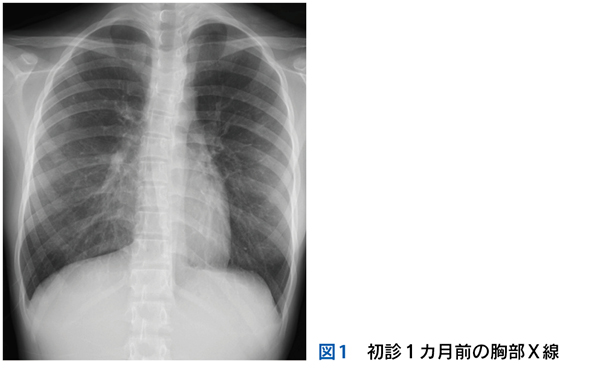

Case 1

独居の高齢者が自宅内で倒れている状態で発見され搬送された。最終健常は5日前。頻脈,SpO2低下,意識障害,感染徴候を伴う褥瘡,急性腎障害,高ナトリウム血症,クレアチンキナーゼ高値,炎症反応亢進,膿尿がみられている。

▶ この患者は何らかのイベントを契機に動けなくなり,長時間倒れていたものと推測される。多数ある「プロブレム」の中には,最初のイベントに直接起因するものもあるかもしれないが,大部分は倒れていた結果として生じてきたもの(最初のイベントの診断という観点では「ノイズ」)だろう。こういった患者が「脱水症」とか「横紋筋融解症」としてのみ治療されているケースをよく見かけるが,これは表層に現れた二次的,三次的な現象を取り上げているだけであり,最初のイベントの鑑別と治療が本来必要である。

Case 2

1カ月続く発熱と消耗のため入院している患者。発熱当初から変更を繰り返しながら抗菌薬が使用されており,現在も2剤併用中。ほかにも対症療法などで複数の薬剤を使用中。血液培養は抗菌薬使用開始後2週間で採取され陰性。経過中,皮疹,肝機能異常,腎障害,汎血球減少が出現している。

▶ こちらは初期評価不十分のまま多数の介入がなされたケースである。患者が呈している「プロブレム」をまとめて,「皮疹,肝機能異常,腎障害,汎血球減少を伴う遷延性発熱」とフレーミングし,たとえば血管内リンパ腫や血球貪食を伴う成人スティル病などを考えることも可能だが,現在の症状や検査異常(の一部)は抗菌薬をはじめとした介入の副作用として生じているのかもしれない。すべてのプロブレムが一元論で説明されない可能性も考慮したフレーミングも用意するのが謙虚な態度だろう。

Case 3

意識障害を呈して搬送された患者の初期検査で,中等度(125mEq/L程度)の低ナトリウム血症が判明した。

▶ ここで「意識障害の原因は低ナトリウム血症である」と考え,この患者の主要問題を「低ナトリウム血症」とフレーミングするかもしれない。しかし,この程度の低ナトリウム血症が意識障害の単一の原因となることは実際には少ないため,低ナトリウム血症は意識障害の診断という観点では「ノイズ」の可能性がある(意識障害は他の病態,たとえば敗血症,脳卒中,薬物中毒などに起因しており,低ナトリウム血症は意識障害とともにそれらの病態の結果なのかもしれない)。したがって,この患者では低ナトリウム血症が同定された後も,「意識障害」というより広いフレーム内にとどまり,他の原因の探索を続けたほうが謙虚で安全である(ただし,低ナトリウム血症自体の評価と治療も当然必要である)。